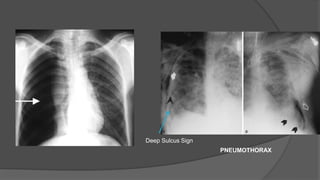

PNEUMOTHORAX

Deep Sulcus Sign

COMPLICATIONS Barotrauma Barotrauma : Associatedwith positive pressure ventilation. Incidence 5 -10% • Pneumothorax • Dyspnea, sharp pleuritic chest pain • Tachypnea, tachycardia • Contralateral tracheal deviation , hyperresonant percussion Subcutaneous and Mediastinal Emphysema

COMPLICATIONS Pneumothorax Treatment ○ Emergent :14 – 16 Gauge i/v needle in 2nd – 3rd IC space (midclavicular line) ○ Definitive : Tube Thoracostomy To be kept in place till < 100 ml fluid drains /day No air leak Lung fully expanded

• #30 Diagnosis : chest radiograph Erect film ideal Deep sulcus sign on supine film Lateral decubitus film for smaller quantities of air Life threating condition tension pneumothorax